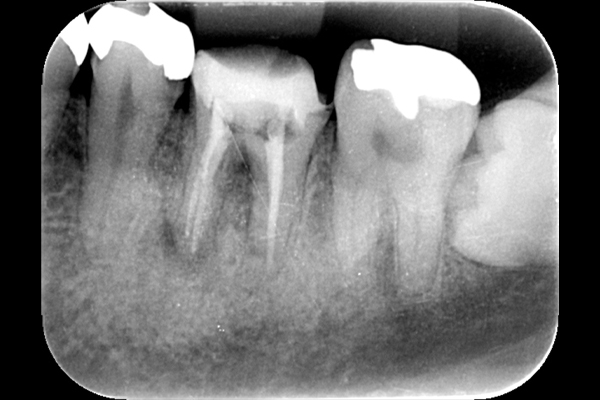

それは歯の先に枝分かれが多く存在し、そこにばい菌が入り込んで難治性となっているからです。ではその場合どうするのか?外科治療をします。その枝分かれの部分を切り落とすのです。今回はその前後のレントゲンの写真をお見せします。

| 根の中の薬が十分に充填されておらず、根の先が周りと比べて黒くなっており、炎症があると判断できます。 | 根の中にしっかりとお薬を緊密に充填しましたが、まだ根の先に黒くなっている部分があります。 |

| 根の先の黒い影は消失しました。 | 術後6ヶ月のCT画像です。こちらでも、根の先に黒い影は見当たらないです。 |

このように外科的治療で病変部を切除することでしっかりと治癒させることが可能です。根の治療は細菌との戦いです。難しいですが、やりがいがあります。